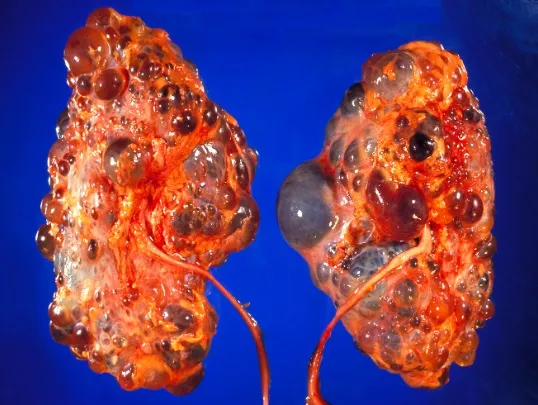

Diálise Peritoneal na Doença Renal Policística: existe algum motivo para não indicar?

Diálise Peritoneal na Doença Renal Policística: existe algum motivo para não indicar?

A DRPAD não é contraindicação à DP — e, na prática, muitos pacientes têm resultados comparáveis à hemodiálise. O “porém” está na mecânica: rins/hepatomegalia podem reduzir tolerância a volumes, aumentar risco de hérnias e extravasamentos, e piorar desconforto respiratório. Com técnica adequada (cateter presternal ou lateral, volumes menores, cicladora noturna e decúbito supino), a maioria das barreiras é contornável. Neste post, revisamos quando a DP é ótima, quando exigir cautela e como ajustar a prescrição para segurança e qualidade de vida.